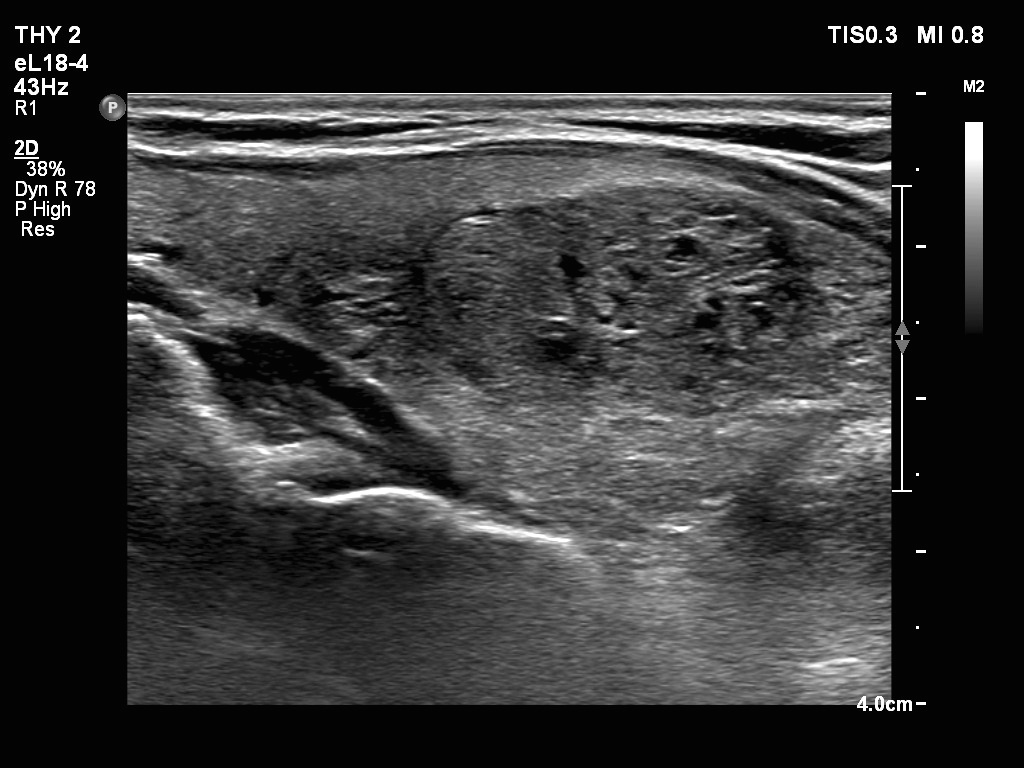

Ultrasonography. The thyroid was echonormal. There were two nodules in the right lobe. The upper was hyperechogenic-cystic while the lower was a minimally-moderately hypoechogenic. The latter had irregular, lobulated margins. There was a hypoechoic area in the upper two-third of left lobe. The discrete area presented ill-defined margins and decreased vascularization. A spongiform cyst was found in the lower pole of the left lobe.

Cytology of the nodule with irregular margins resulted in benign lesion, while cytology disclosed de Quervain's thyroiditis in the event of the hypoechoic area in the left lobe.